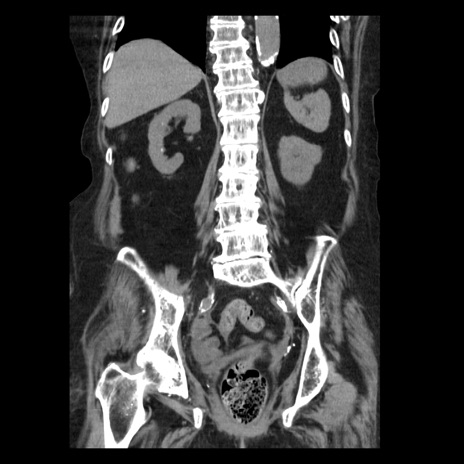

症例14(冠状断像)

【症例】 90歳代女性

【主訴】 腹痛・嘔吐

【現病歴】今朝から左側腹部痛を認めた。 経過観察していたが、嘔吐を認めたため来院。

【既往歴】 子宮癌術後

【身体所見】 意識清明、BP 127/54mmHg、P 98bpm Sp02 95%(RA)、BT 35.8°C、腹部平坦・軟腸ぜん動音聴取良好、右下腹部圧痛(+) 反跳痛なし

【データ】WBC 9800、CRP 0.46